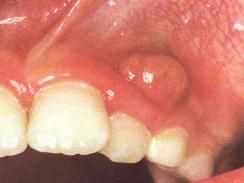

早期患牙有輕度疼痛,此時患牙咬緊,疼痛可以暫時緩解,隨炎症加重,患者齒伸長,有浮出感,輕叩患牙即疼痛。根尖周炎時疼痛為自發性、持續性癌,且範圍局限,患者能明確指出患牙。 如果急性根尖周炎沒有得到治療,炎症繼續發展,形成急性根尖膿腫,則疼痛加劇,叩痛明顯,且有持續性跳痛。膿液擴散至骨膜下,疼痛、腫脹均很明顯,膿液一旦穿破骨膜達到黏膜下,由於壓力減弱,黏膜下組織疏鬆,疼痛比以前減輕。